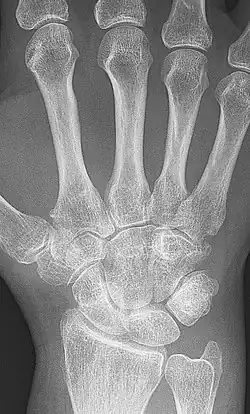

X-ray of the wrist of a woman with rheumatoid arthritis, showing unaffected carpal bones in the left image, and ankylosing fusion of the carpal bones eight years later in the right image

X-rays of the hands and feet are generally performed when many joints are affected. In RA, there may be no changes in the early stages of the disease, or the X-ray may show osteopenia near the joint, soft tissue swelling, and a smaller than normal joint space. As the disease advances, there may be bony erosions and subluxation. Other medical imaging techniques such as magnetic resonance imaging (MRI) and ultrasound are also used in RA.[20][79]